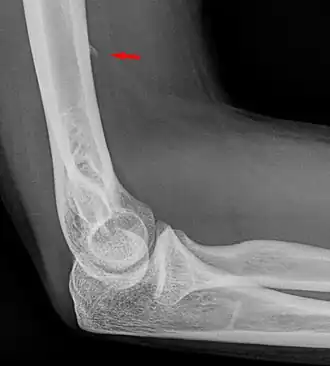

Small supracondylar process seen on a lateral radiograph of the elbow

The supracondylar process of the humerus (also known as an avian spur) is a variant bony projection on the anteromedial aspect of the upper arm bone (humerus), about 5–6 cm above the medial epicondyle.[1] It is directed downward, forward and medially pointing to the medial epicondyle. A fibrous band, Struthers ligament, may connect this process to the medial epicondyle.[2] This variation has a prevalence of 0.68% and is significantly more common in women than in men.[3]